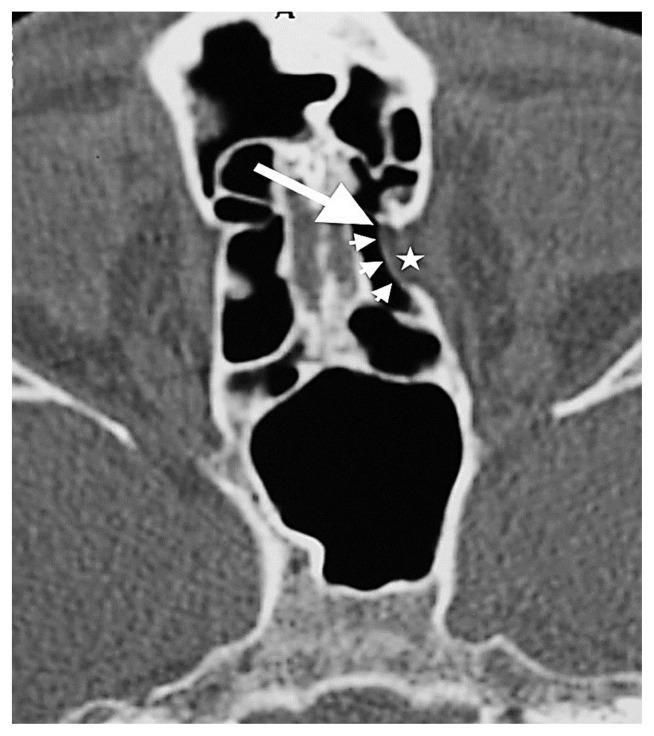

BACKGROUND/AIM: The aims of this study are to determine the incidence and more frequent localizations of orbital fat tissue herniation accompanying dehiscences in the medial orbital wall and to investigate the relationship between orbital fat tissue herniations and the anterior and posterior ethmoidal foramina.

One thousand two hundred patients who had undergone computed tomography with a preliminary diagnosis of sinusitis and who had no previous facial, orbital, paranasal sinus surgeries or history of trauma were retrospectively analyzed. The localization of the ethmoidal foramina and orbital fat tissue herniations were marked. In patients with orbital fat tissue herniation, the relationship between the localization of orbital fat tissue herniation and the anterior and posterior ethmoidal foramina was investigated.

The incidence of orbital adipose tissue herniation in our study was 7.9%. Of the 98 herniations on the bilateral medial orbital wall, 60 were in zone 3, and the most common herniation site was zone 3. A statistically significant difference was noted between the localization zone of the anterior ethmoidal foramen and the localization zones of orbital fat tissue herniations (Fisher's exact test, p < 0.001).

Zone 3 is the weakest area of the medial orbital wall, and zone 3 is the most prone to herniation of fat tissue. The association of orbital fat tissue herniations with the anterior ethmoidal foramen is extremely common. Being cognizant of this finding may help a surgeon better estimate the anatomical view to be met before functional endoscopic sinus surgery as well as to minimize the risk of possible orbital complications, especially anterior ethmoidal artery injury.

背景/目的:本研究的目的是确定眶内侧壁裂开伴发眶脂肪组织疝出的发生率及更常见的部位,并研究眶脂肪组织疝出与筛前孔和筛后孔之间的关系。

回顾性分析1200例初步诊断为鼻窦炎且既往无面部、眼眶、鼻窦手术史或外伤史的患者的计算机断层扫描结果。标记筛孔和眶脂肪组织疝出的部位。对于有眶脂肪组织疝出的患者,研究眶脂肪组织疝出部位与筛前孔和筛后孔之间的关系。

本研究中眶脂肪组织疝出的发生率为7.9%。在双侧眶内侧壁的98处疝出中,60处位于3区,最常见的疝出部位是3区。筛前孔的定位区与眶脂肪组织疝出的定位区之间存在统计学显著差异(Fisher精确检验,p<0.001)。

3区是眶内侧壁最薄弱的区域,3区最容易发生脂肪组织疝出。眶脂肪组织疝出与筛前孔的关联极为常见。认识到这一发现可能有助于外科医生在功能性鼻内镜鼻窦手术前更好地估计可能遇到的解剖情况,并将可能的眼眶并发症风险降至最低,尤其是筛前动脉损伤。